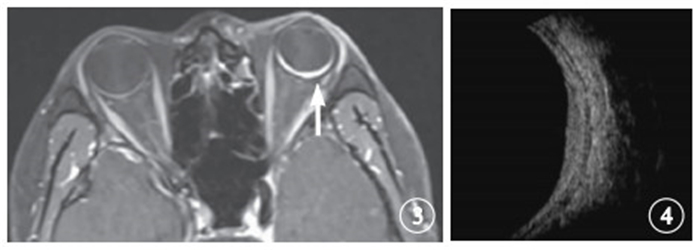

末次隨訪時,腫瘤體積1.24~2.16 cm3,腫瘤體積中位數1.68 cm3,腫瘤平均體積(1.68±0.30) cm3。與治療前比較,治療后腫瘤體積縮小14.6%~72.7%,平均縮小(44.89±21.30)%(圖 3,4)。

末次隨訪時,腫瘤體積1.24~2.16 cm3,腫瘤體積中位數1.68 cm3,腫瘤平均體積(1.68±0.30) cm3。與治療前比較,治療后腫瘤體積縮小14.6%~72.7%,平均縮小(44.89±21.30)%(圖 3,4)。